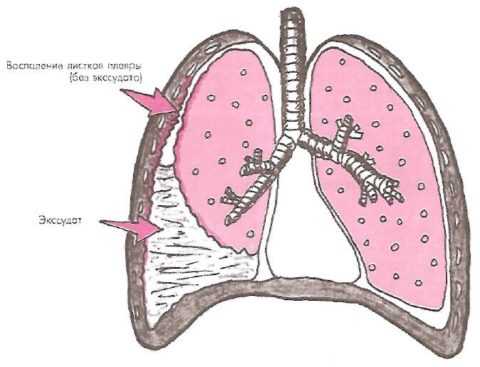

![]() Плеврит | Воспаление плевральной оболочки, сопровождающееся накоплением в ней жидкости. |

Плеврит

Следствием травмы грудной клетки также может стать воспаление плевральной оболочки легких. При посттравматическом плеврите скапливается жидкость в легких после перелома ребер.

Это опасное состояние, так как возникает дефицит кислорода, нарушение сердечного ритма. При прогрессировании процесса воспаление распространяется на соседние ткани, дыхательная деятельность сильно затрудняется, может развиться отек легкого.

Чтобы не допустить осложнений, в частности, летального исхода, необходимо откачать жидкость из легких. Дополнительно назначаются противовоспалительные, гипосеснибилизирующие препараты, антибиотики.